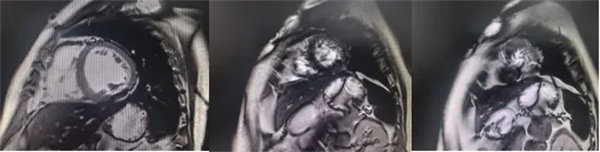

在常规心脏MRI检查中,医学影像科发现患者心肌异常表现,考虑铁过载性心肌病,为明确诊断要进一步加做铁定量技术,加扫T2 mapping序列。CMR铁定量技术是目前评估心肌铁含量的“金标准”,能够快速、无创、精准量化心肌内铁沉积程度,检查结果提示患者局部心肌T2*值显著低于正常范围,符合铁过载性心肌病的诊断标准。

基底部、中间部及心尖部 局部心肌T2*值明显减低T2* 10-20/s, 部分小于10/s

心肌信号局部减低 呈现“黑色心肌”表现,这是由于铁沉积导致局部磁场不均匀,引起信号丢失(失相位)。